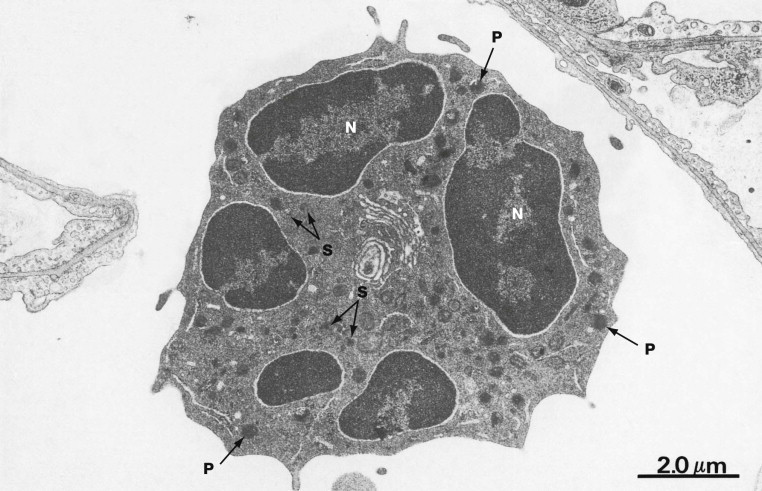

What is this cell?

Lymphocyte